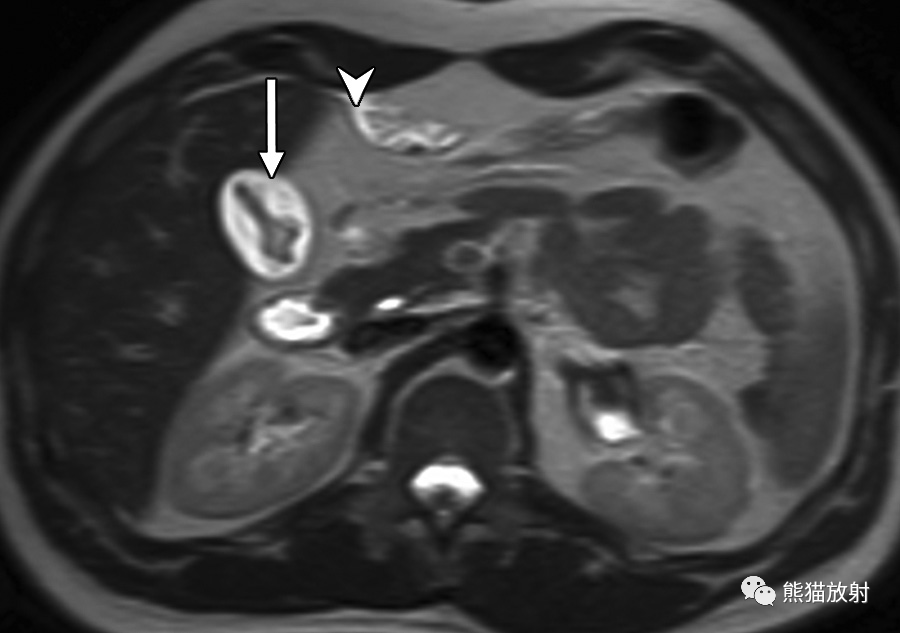

65岁男性,因急性坏疽性胆囊炎发生化脓性肝脓肿。(a)轴位T2WI显示脓肿壁的双靶征,表现为围绕脓肿内部高信号内容物的等低信号内层(箭头)和中等高信号外层(箭)。注意胆囊颈部嵌顿的低信号结石 (*)。(b)轴位对比增强动脉期脂肪抑制T1WI图像显示内层早期强化(箭头)和邻近节段性肝实质充血。(c)轴位对比增强延迟期图像显示内层和外层延迟强化(箭)。

55岁男性,肝移植后1年,肺炎克雷伯菌脓肿。(a)轴向对比增强CT图像显示化脓性肝脓肿内有气体(箭)。(b)轴位梯度回波反相T1WI图像显示脓肿内无信号的气体(箭),与结肠内气体的表现相似(*)。(c)同相位T1WI显示由于气体磁化率效应增强脓肿内出现光晕伪影(箭),在邻近结肠中也观察到伪影(*)。(d)DWI (b = 800s/mm2) 显示由于水扩散受限,脓肿内部呈高信号(箭)。(e) 相应的ADC图显示扩散系数降低,表现为脓肿内的低信号(箭)。

“绿松石征”和肝脓肿一过性节段性强化。(a)轴位T2WI显示肝左叶肝脓肿,内部高信号并大量树枝样间隔(箭),表现类似绿松石。(b)轴位脂肪抑制T1WI平扫显示低信号局灶性肝脏病变。(c)对比增强动脉期病灶周围高强化(箭头)和内部分隔强化(箭)。(d)延迟期可见内部分隔持续强化(箭)。脓肿内容物抽吸培养物有肺炎克雷伯菌生长。